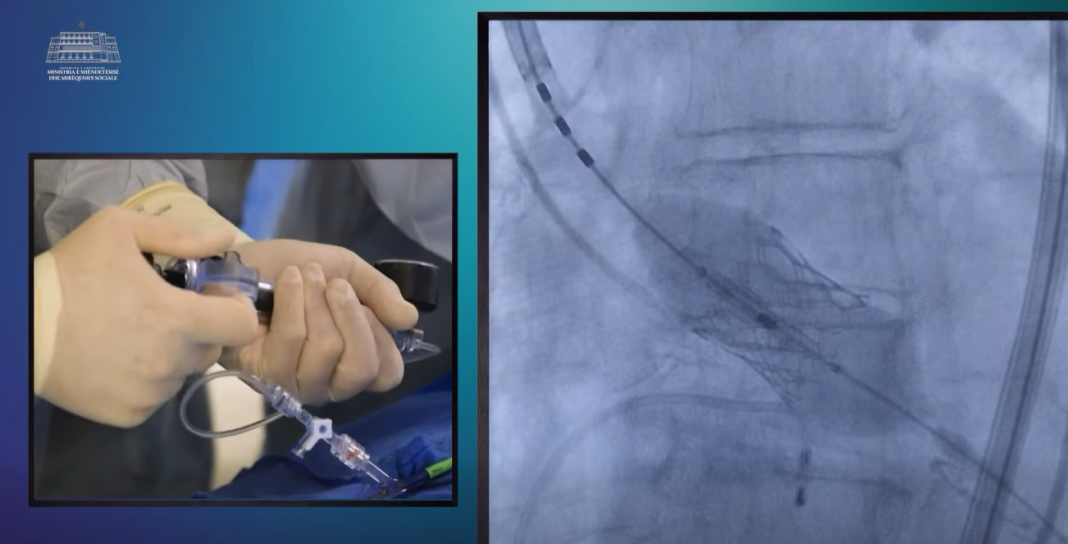

Ministria e Shëndetësisë dhe Mirëqenies Sociale njoftoi sot se në Qendrën Spitalore Universitare “Shefqet Ndroqi” është realizuar me sukses ndërhyrja për zëvendësimin e valvulës aortale të dëmtuar, përmes përdorimit të teknikës moderne miniinvazive.

Ministria e Shëndetësisë dhe Mirëqenies Sociale njoftoi sot se në Qendrën Spitalore Universitare “Shefqet Ndroqi” është realizuar me sukses ndërhyrja për zëvendësimin e valvulës aortale të dëmtuar, përmes përdorimit të teknikës moderne miniinvazive.

Dr. Merito Siqeca, kardiolog invaziv pranë SU “Shefqet Ndroqi”, tha se tavi është një procedurë minimalisht invazive, me anë të së cilës realizohet zëvendësimi i valvulës aortale të dëmtuar.

“Kjo procedurë realizohet me rrugë transfemorale, pra nga arteria e rrëzës së kofshës”, tha Siqeca, ndërsa konfirmoi se në sistemin shëndetësor publik në Shqipëri janë vetëm dy raste të realizuara me këtë metodë.

“Përfitimet më të mëdha të kësaj procedure janë që pacienti e shmang çarjen e madhe në mes të gjoksit dhe gjaku nuk kalon në qarkullim jashtëtrupor gjatë procedurës”, tha ai.

“Tavi, kjo procedurë që është miniinvazive i ndihmon shumë këta pacientë që e kanë të pamundur të bëjnë kirurgjinë e hapur. Një nga pacientët tanë që kishte probleme me veshkën dhe ishte e pamundur që të ndërhyhej me hapjen e gjoksit, u realizua përmes kësaj teknike dhe doli me sukses”, pohoi Meshi.